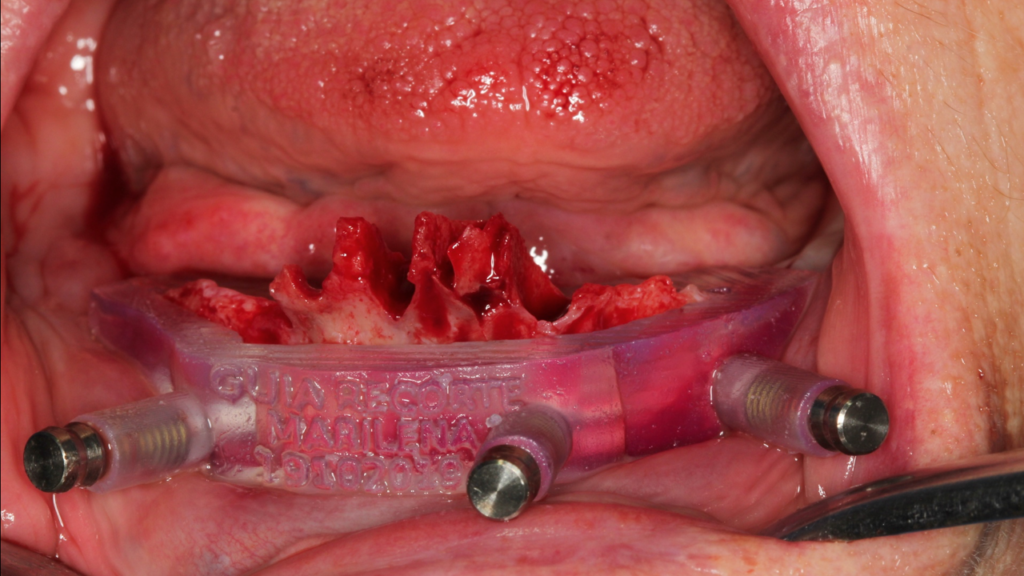

Paciente do sexo feminino, 82 anos, com a presença de dentes anteriores de mandíbula usando prótese móvel na região posterior por mais de 30 anos. Com isso, a reabsorção óssea posterior causou um desnível muito grande em relação à região anterior.

Através do programa Blue Sky (em parceria com a empresa Odontoplanning), foi feito planejamento guiado com 2 guias. O primeiro guia de recorte ósseo, tem como objetivo o recorte e aplainamento ósseo, deixando uma altura óssea mais uniforme entre a região posterior e anterior da mandíbula.

Através da imagem do osso recortado é planejada a guia de perfuração que vai se encaixar de uma maneira perfeita no osso recortado.

Lembrando que essas guias serão apoiadas exclusivamente no osso, sem envolvimento de mucosa, portanto há que se fazer incisão e descolamento mucoperiostal suficiente para o encaixe da guia.